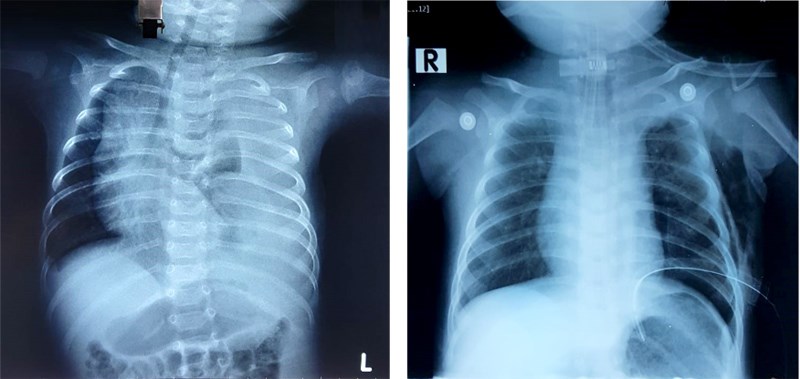

XQuang trước mổ (ảnh trái): Phổi bên trái có nhiều dịch, trắng xóa cả bên phổi. XQuang sau mổ (ảnh phải): Không còn dịch, phổi nở hoàn toàn

Bệnh nhi nhập viện trong tình trạng khó thở nặng. Kết quả phim chụp X quang phổi của bé cho thấy tình trạng tràn dịch màng phổi bên trái với lượng dịch nhiều. Kết quả xét nghiệm dịch màng phổi phát hiện bệnh nhi bị rò dịch dưỡng trấp nghi do rò từ ống ngực vào khoang màng phổi.